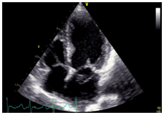

Her echocardiogram showed mild left ventricular and left atrial dilatation with normal left ventricular systolic function. The mitral valve was morphologically abnormal with the anterior mitral leaflet showing an cystic aneurysmal segment with systolic ballooning and some degree of diastolic collapse but incomplete collapse. (Figures 1-3) (Video 1) (Video 2) The aneurysmal segment showed a classical heart shape which was most evident in the end systolic frame. Colour flow imaging showed severe mitral regurgitation with an eccentric jet, the origin of the jet appeared to be through the anterior mitral leaflet. The transeosopheal echocardiography revealed similar findings (Figure 4) (Figure 5)The aortic valve was morphologically normal but for mild cuspal thickening.

Figure 1 The cystic mass on the mitral valve in diastole.